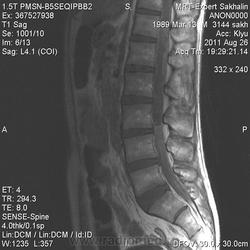

Здравствуйте,уважаемые коллеги! При сирингомиелии кистозные полости локализуются в спинном мозге, в данном же случае явно визуализируется новообразование от уровня межпозвонкового диска ТН11-ТН12 до L4 позвонка.Спинной мозг же прослеживается обычно до L1 позвонка. Предлагаю такой вариант-эпендимома конуса спинного мозга и корешков конского хвоста.

Интрамедуллярная опухоль. Эпендимома? Сирингомиелитические кисты.

Клиника больше на образование тянет.Я обратила внимание на изменения МР-сигнала выше, на уровне грудного отдела, но парень еле смог вылежать , поэтому поговорили с лечащим врачом и решили, что позже привезут на ГОП.

На протяжении Th12-L3 есть изменение сигнала интрамедуллярно... Интересно, пойду почитаю...